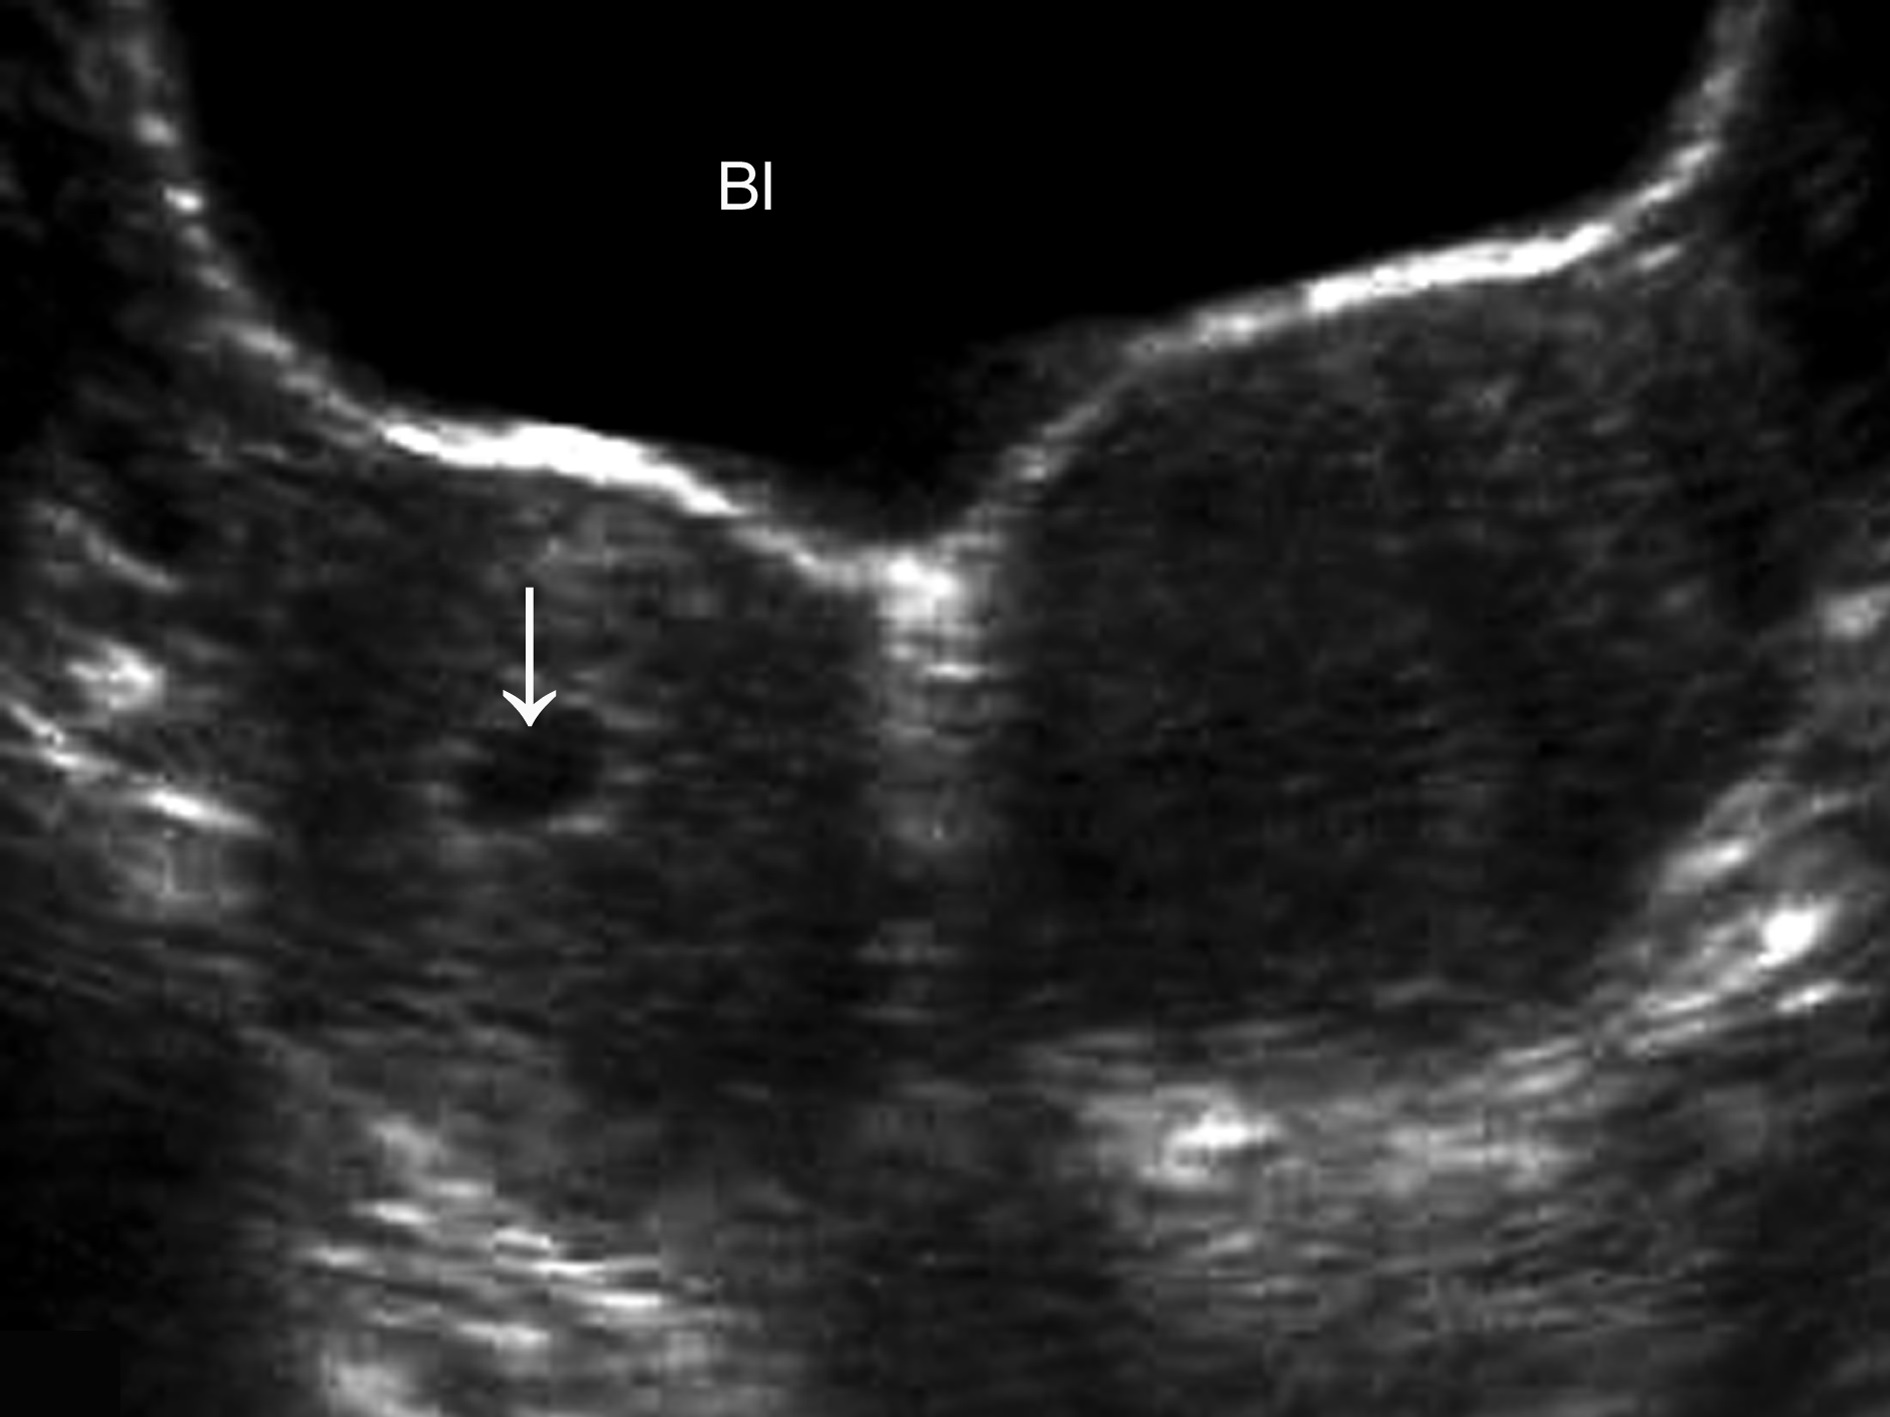

早期妊娠超声显象检查可以显示双侧的子宫体,其中之一内可见孕囊及胚胎回声,另一侧子宫明显增大(图2),内膜回声增强、增厚,有时可在未妊娠的一侧子宫腔内显示细长的无回声区或由增厚的蜕膜形成的强回声。在做出双子宫、一侧子宫妊娠的诊断时应当注意与妊娠合并子宫肌瘤、残角子宫等进行鉴别。一般情况下,子宫肌瘤与子宫肌壁回声有一定的差异,或回声增强,或回声降低,内部很少可以显示规则的囊状无回声区。如果在双侧子宫内均显示孕囊回声,则为双子宫、双侧妊娠(图3)。

图2双子宫单侧妊娠(箭头)声像图